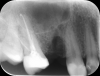

DmitrySH Опубликовано 16 августа, 2013 Поделиться Опубликовано 16 августа, 2013 Костные структуры в области шестого зуба не позволяют адекватно видеть его состояние. К щечным корням шестого зуба есть вопросы. Лечение желательно, но вот он создает проблему или нет - сложно сказать. Желательно сделать КТ. Ссылка на комментарий

juli63 Опубликовано 17 августа, 2013 Поделиться Опубликовано 17 августа, 2013 6 зуб нуждается в эндодонтическом лечении. Ссылка на комментарий

Маруся34 Опубликовано 17 августа, 2013 Автор Поделиться Опубликовано 17 августа, 2013 6 зуб нуждается в эндодонтическом лечении.А что там не так? Мне сказали, что есть перфорация корня, ничего уже не сделать. Мол, если будет беспокоить, то удалять, а так мол, живите дальше. Ссылка на комментарий